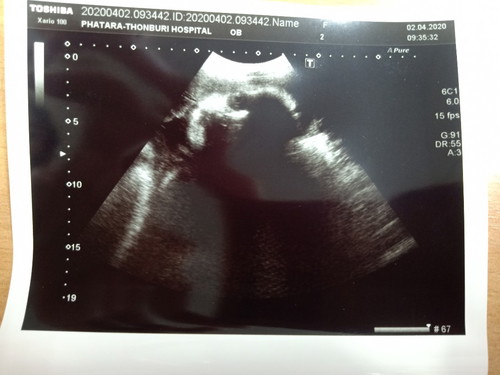

วันนี้หมอนัดครบ 31W2D น้องน้ำหนัก 2,200 กรัม หมอบอกว่าแอบตัวใหญ่นะเนี่ย ดูเหมือนท้องจะไม่ใหญ่ ตอนนี้กลับหัวแล้ว แม่เดินจะไม่ไหวแล้วค่ะ อยากเจอหน้าแล้วตอนนี้ แม่ๆเดือน มิ.ย. ไปถึงใหนกันแล้วคะ บ้านนี้กำหนด 2มิ.ย.